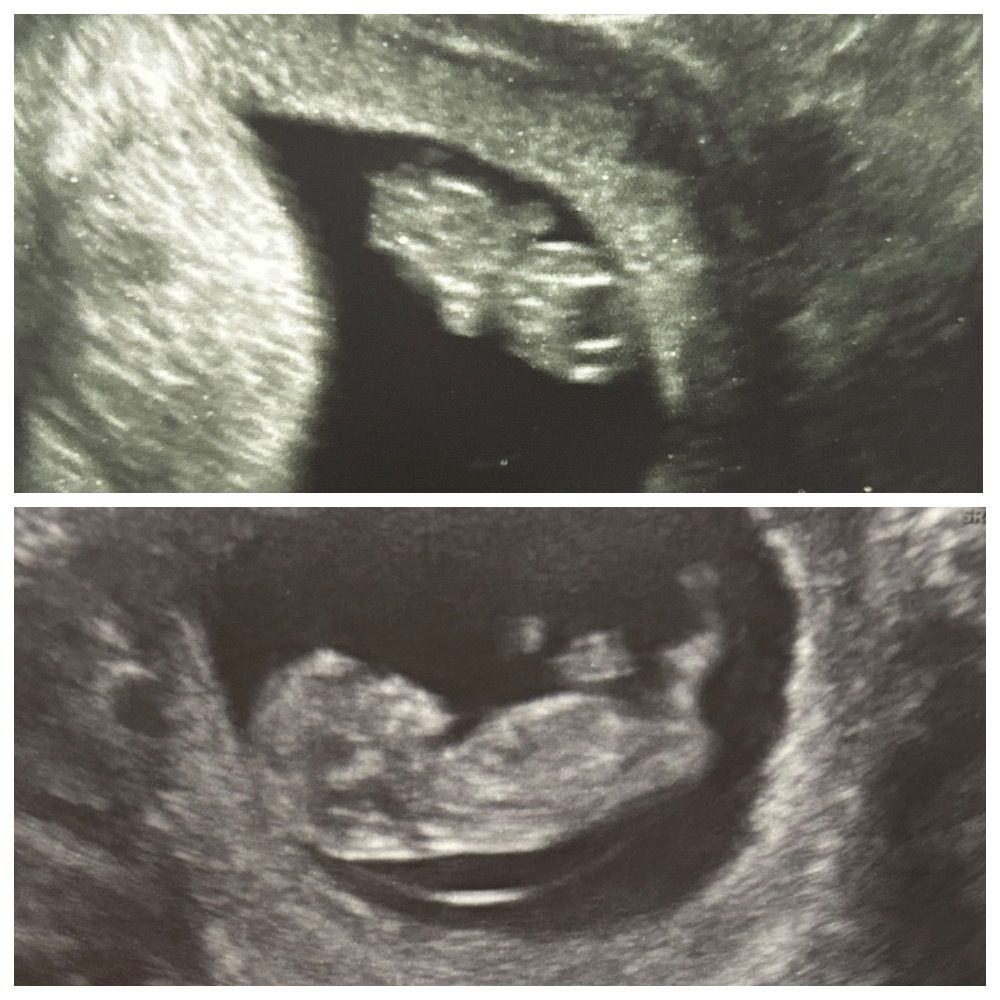

УЗИ в 11 недель

Пишу, скорее, для себя, потом перечитывать хронологию) сходила на узи платно, думала смогут скрининг сделать, сегодня как раз 11 недель, но малышу не хватило 3мм 😂 надо, чтобы ктр был хотя бы 45мм, а у него 42мм, но зато поставили 11 недель по узи и 1 день. Опережает на денёк развитие. В целом, сказала визуально все хорошо, кости черепа сформированы правильно, глаза на месте, ручки-ножки на месте, говорит и твп и назальная кость визуально хорошие (я ей доверяю, всю первую беременность, помимо жк, платно к ней бегала узи делала с дочкой) в общем, жду 15 числа, будет 12 недель, скрининг бесплатный будет. За 2 недели прогресс огромный у малыша 😁 фото прилагаю 9 недель и 11. Цикл не регулярный, поэтому 13 недель это по месячным, но по ним не ориентируемся) переживаю за шейку, в 9 недель была 39мм, сейчас 34, но вроде тоже норма, может, погрешность измерений) и переживаю за то, что плацента прям на рубце, что в 9 недкль, что сейчас в 11, надеюсь, поднимется.